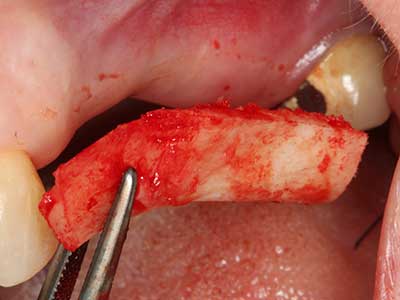

Bone tissue is not simply a mineral structure but also contains a substantial proportion of collagen fibres. This means it not only has good compressive strength but also a degree of flexibility, which can be taken advantage of when performing bone augmentations. In the classical expansion procedure using bone splitting, the atrophied alveolar ridge is split longitudinally and carefully expanded after reaching an adequate osteotomy depth (Fig. 13-16), ideally without substantial removal of the periosteum (Brugnami, Caiazzo et al. 2014, Stricker, Fleiner et al. 2014). Screw and plate systems with increasing expansion distance have proven effective in separating the two bone lamellae while remaining below the fracture threshold. In general, residual bone widths of at least 3–4 mm are required (Chiapasco, Zaniboni et al. 2006) to guarantee adequate flexibility and sufficient bone coverage of the future implants. If necessary, a vertical relief osteotomy on one or both sides can improve flexibility. A combination with additional augmentation techniques, particularly on the buccal side, has been described as an alternative to the classical technique.